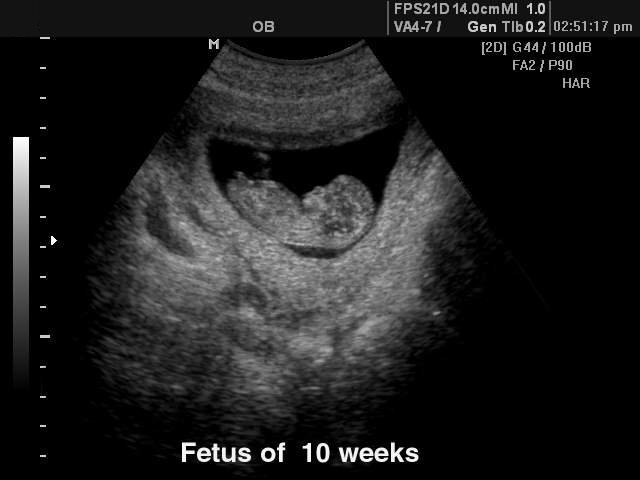

Плод в 10 недель беременности